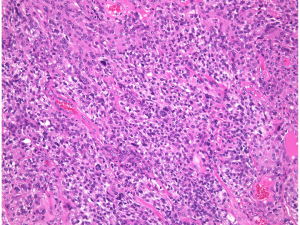

atypical meningioma WHO grade 2(長嶋和郎先生の病理教室)

高齢者の後頭窩 (ptrous ridge) にみられた大きな髄膜腫でした。meningiomaと考えられますが、whorl patternやmeningothelial featureなど特徴的なpatternが見られずpattern lessと見做されます。さらに、腫大しchromatinに富む核が見られ、異型細胞と考えられます。

EMAが陽性となることでmeningiomaが示唆されます(左:EMA染色 x200x)。腫瘍の一部でcollagen fiberの多い組織に移行し、核の消失を伴う壊死性変化を示す部位が見られます。

腫瘍の周辺部にonion bulb構造 (→)が見られ、meningiomaの診断が妥当です(左)。細胞核の異型性がありMIB-1 indexが10%と高値であり(右)、atypical meningiomaです。